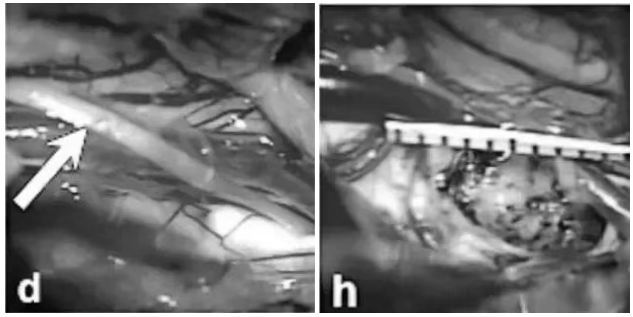

术中发现,在滑车神经水平,被盖表面明显膨隆(箭头,图d),这正是出血病灶压迫的表现。在显微镜下,凭借精湛的技术和极大的耐心,巴教授及其手术团队成功地将致病的海绵状血管畸形病灶完整切除!术后复查影像和详实的手术记录都明确证实了病灶的全切。

术中记录(图d-h)